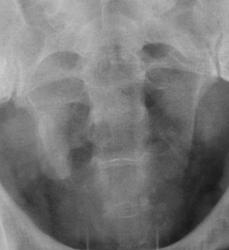

Пациент с диагнозом "МКБ" направлен на обзорную рентгенографию почек и мочевыводящих путей.

Пациент с диагнозом "МКБ" направлен на обзорную рентгенографию

Внутривенная урография.

На мой взгляд дополнительная интенсивная тень лежит за контуром почки. В проекции Желчного пузыря. Так что желчекаменная болезнь? Рекомендованно УЗИ печени и желчного пузыря.

Да с камнем желчного то все понятно...но вот тень в проекции н\трети правого мочеточника ....весьма необычна...вопрос - куда ее "пристроить"?))))

Я не про "утверждаю", Боже спаси, для мочеточника тень очень больших размеров, хотя расположена вдоль его проекционной оси, но здесь же проекция крупных сосудов, стенты сейчас могут быть всякими разными, а потом-в малом тазу не только у женщин, но и мужчин хватает всякого, что может обызвествляться. А верхняя тень-типично для желчного пузыря.

Да, камешек для желчного типичный.

А тень в дистальной трети мочеточника действительно "фердиперсовая"...